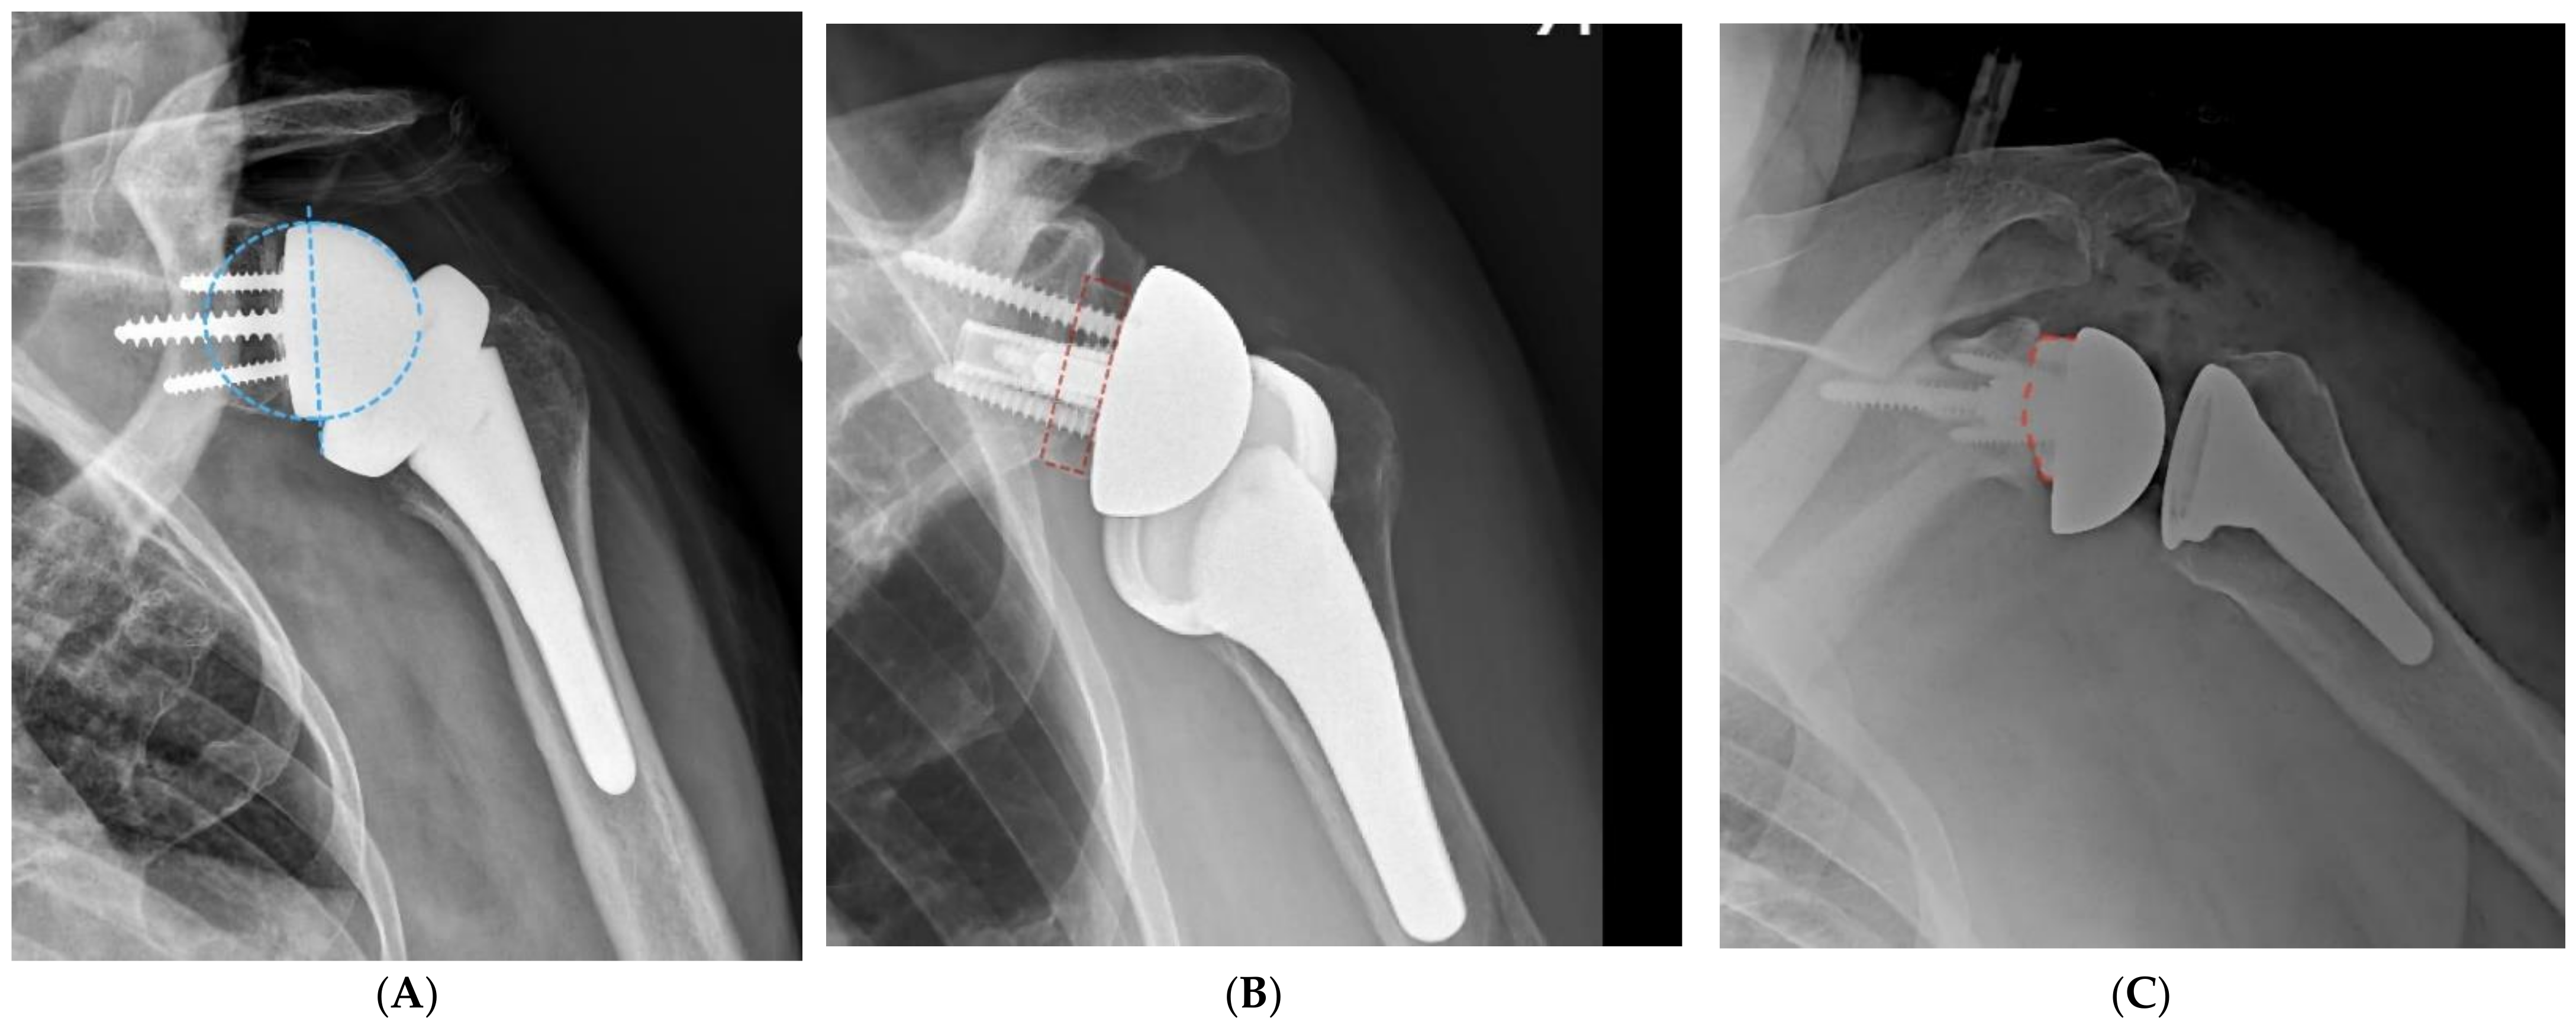

Avoiding any impingement between the medial aspect of the polyethylene and the body of the scapula and scapular pillar essentially requires displacing the proximal humerus laterally and posteroinferiorly. This is best achieved by implanting a larger glenosphere with a posteroinferior overhang in reference to the glenoid vault combined with a larger lateral offset of the glenoid component. Larger lateral offsets may be achieved with thicker glenospheres, structural bone grating between the native glenoid and the baseplate (bio-RSA), or thicker (augmented) baseplates (Figure 4). The benefit of bio-RSA and augmented baseplates over thicker glenospheres is that both bone graft and metal augments provide adequate correction of angular deformities (inclination and retroversion) without reaming excessively, which can lead to impingement as well.

Figure 4.

(A), Impingement-free range of motion is optimized with implantation of larger glenospheres with a lateral offset and an inferior overhang. Glenoid lateralization may be achieved with thicker glenospheres (B), the use of a bone graft under the baseplate (BIO-RSA), or the use of augmented baseplates (C).